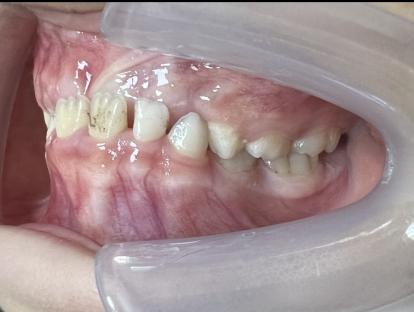

案例二:

治疗前

治疗后